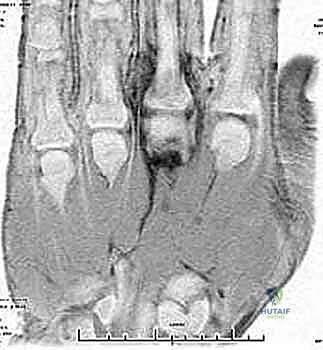

التهاب المفاصل الإنتاني في اليد والمعصم الأسباب الأعراض والعلاج المتقدم مع الأستاذ الدكتور محمد هطيف

اكتشف كل ما يخص التهاب المفاصل الإنتاني في اليد والمعصم، من الأسباب والأعراض إلى التشخيص والعلاج الجراحي المتخصص على يد الأستاذ الدكتور محم…